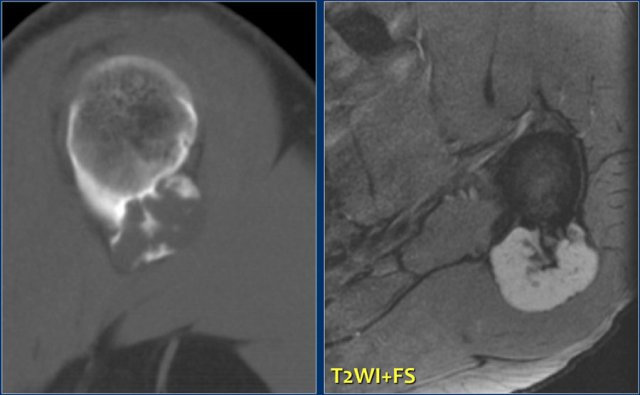

Periosteal or juxtacortical chondrosarcoma

A juxtacortical chondrosarcoma has be considered in the differential diagnosis when a mineralized lesion adjacent to the cortical bone is seen.

Here a partially calcified mass against the proximal humerus with involvement of the cortical bone on an axial CT image.

T2-weighted MR image reveals a lobulated mass with high signal intensity.

The bone marrow compartment is not involved which is important for the surgical strategy.

A periosteal chondroma may have the same imaging characteristics, however, these are almost always much smaller.

Plain radiograph in another patient shows irreglar mineralized lesion with elevation of the periosteum and cortical involvement. On the right T2-WI with FS of same patient.. The juxtacortical mass has a high SI and lobulated contours. DD: juxtacortical chondrosarcoma, parosteal osteosarcoma.